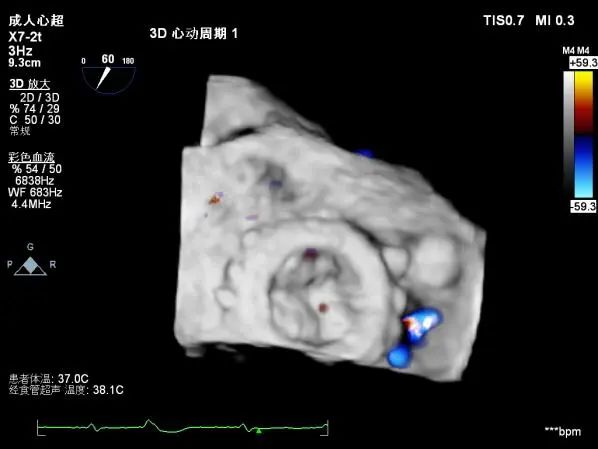

术中及术后食道超声示:

术后食道超声

食道超声示:人工二尖瓣功能良好,无反流,封堵后瓣周反流基本消失。